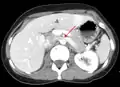

تخثر في الوريد الكلوي الأيسر مع توسعه.